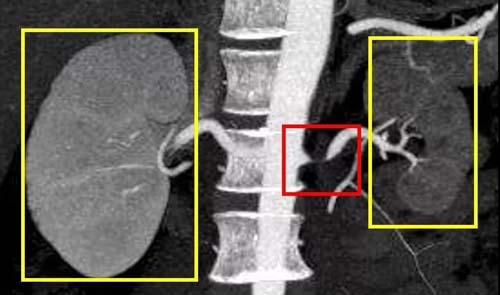

肾动脉狭窄引起肾脏体积缩小

磁共振血管造影(MRA)因耗时时间长、价格较昂贵,相对较少应用,但它可能用于轻度至中度但不严重的肾脏疾病患者,以避免造影剂带来的肾功能损伤。

肾动脉血管造影是检测肾血管狭窄程度的最佳检查方法。但是它是侵入性检查(将导管插入体内),一般和治疗同步进行。